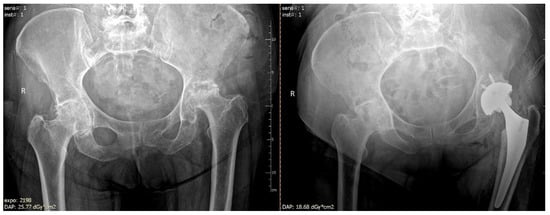

Figure 1 and Figure 2 present AVN of the femoral head developed after surgical stabilization of an intertrochanteric fracture of the femoral bone.

Figure 1. Avascular necrosis of right femoral head following stabilization of intertrochanteric fracture. (A) Posteroanterior view of the fracture; posteroanterior (B) view after 12 weeks of procedure; (C) view at a follow-up visit 20 weeks after the procedure, prominent necrosis of right femoral head; R—right.